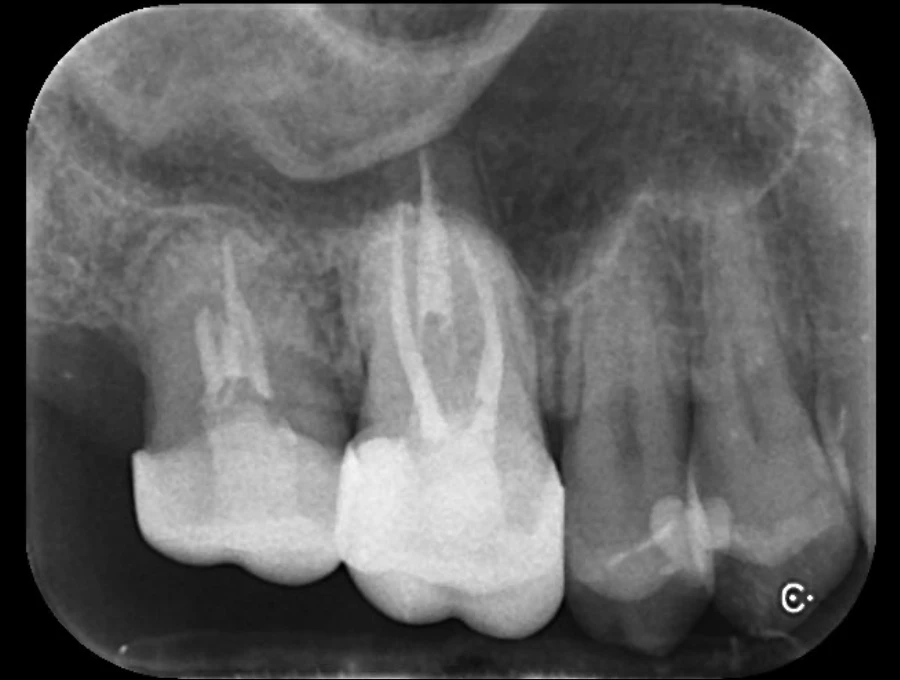

精密検査

実際にお口の中の状態をチェックしていきます。レントゲン撮影にて歯や骨の検査を行い、虫歯や治療痕のチェック、歯周病検査などの各種検査を行い、総合的な診断を下します。

歯周病により破壊された、歯茎や骨を人工骨や成長因子などを用いて再生させる治療方法です。

将来的に抜歯となるリスクの高い歯などを歯周組織を再生させ、歯を長持ちさせることを目的とします。歯周病でダメになった歯をどうしても残したい方、歯ぐきや歯槽骨を元に戻して歯の寿命をしっかり伸ばしたい方に適応される治療方法です。 -